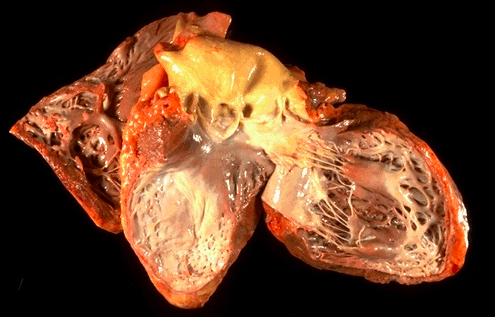

10

Q

What do you see?

A

- Heart is opened to reveal the left ventricular free wall on the right and the septum in the center. There has been a remote myocardial infarction that extensively involved the anterior left ventricular free wall and septum

- The white appearance of the endocardial surface indicates the extensive scarring